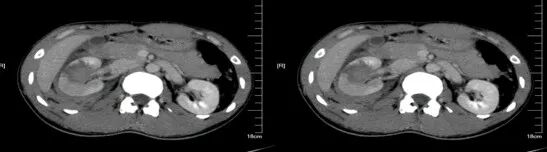

脾挫裂伤

病因病理

脾挫裂伤主要是指腹部受到外在力量的撞击而产生的闭合性损伤,是常见的腹部严重创伤,多由高处坠落、交通意外等引起。

临床表现

患者可有患部疼痛,但严重者多以失血性休克、腹部膨隆为首发症状。